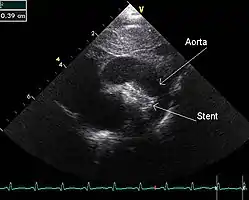

PDA is usually diagnosed using noninvasive techniques. Echocardiography (in which sound waves are used to capture the motion of the heart) and associated Doppler studies are the primary methods of detecting PDA. Electrocardiography (ECG), in which electrodes are used to record the electrical activity of the heart, is not particularly helpful as no specific rhythms or ECG patterns can be used to detect PDA.[8]

Patent ductus arteriosus An echocardiogram of a stented persisting ductus arteriosus: One can see the aortic arch and the stent leaving. The pulmonary artery is not seen.

An echocardiogram of a stented persisting ductus arteriosus: One can see the aortic arch and the stent leaving. The pulmonary artery is not seen. An echocardiogram of a coiled persisting ductus arteriosus: One can see the aortic arch, the pulmonary artery, and the coil between them.